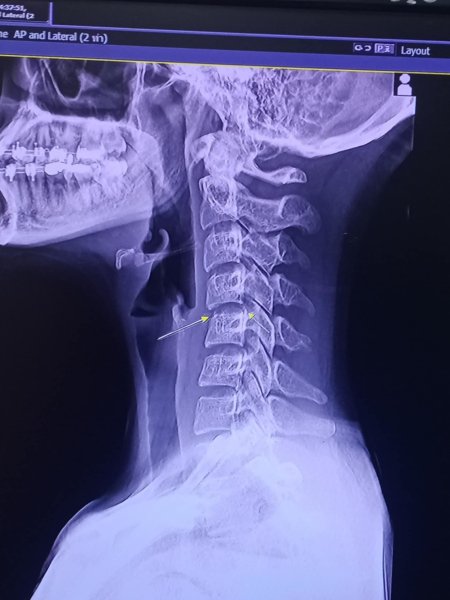

Преди да бъде хоспитализирана, на 5 ноември, Пинг Чаяда публикува рентгенова снимка на шията си и описа влошаващото се състояние в бележка във Facebook до своите 22 000 последователи, пише The Economic Times.

"Първия път, когато бях на масаж, симптомите бяха нормални. Отидох на втори: същият терапевт, в същата стая, този път ми изви врата. След две седмици започнах да имам много, много силни болки, толкова много, че не можех да лежа нито по гръб, нито по корем. Отидох отново, но нов масажист ме притисна много, появиха се синини и отоци, които не изчезнаха в продължение на една седмица, постоянно пиех лекарства за облекчаване на симптомите. Разбрах, че дясната ми страна е изтръпнала, не можех да си вдигна дясната ръка. Искам да оставя това като урок за тези, които наистина обичат масажа. Оздравявам. толкова много искам да работа, но просто чакам подходящия момент.